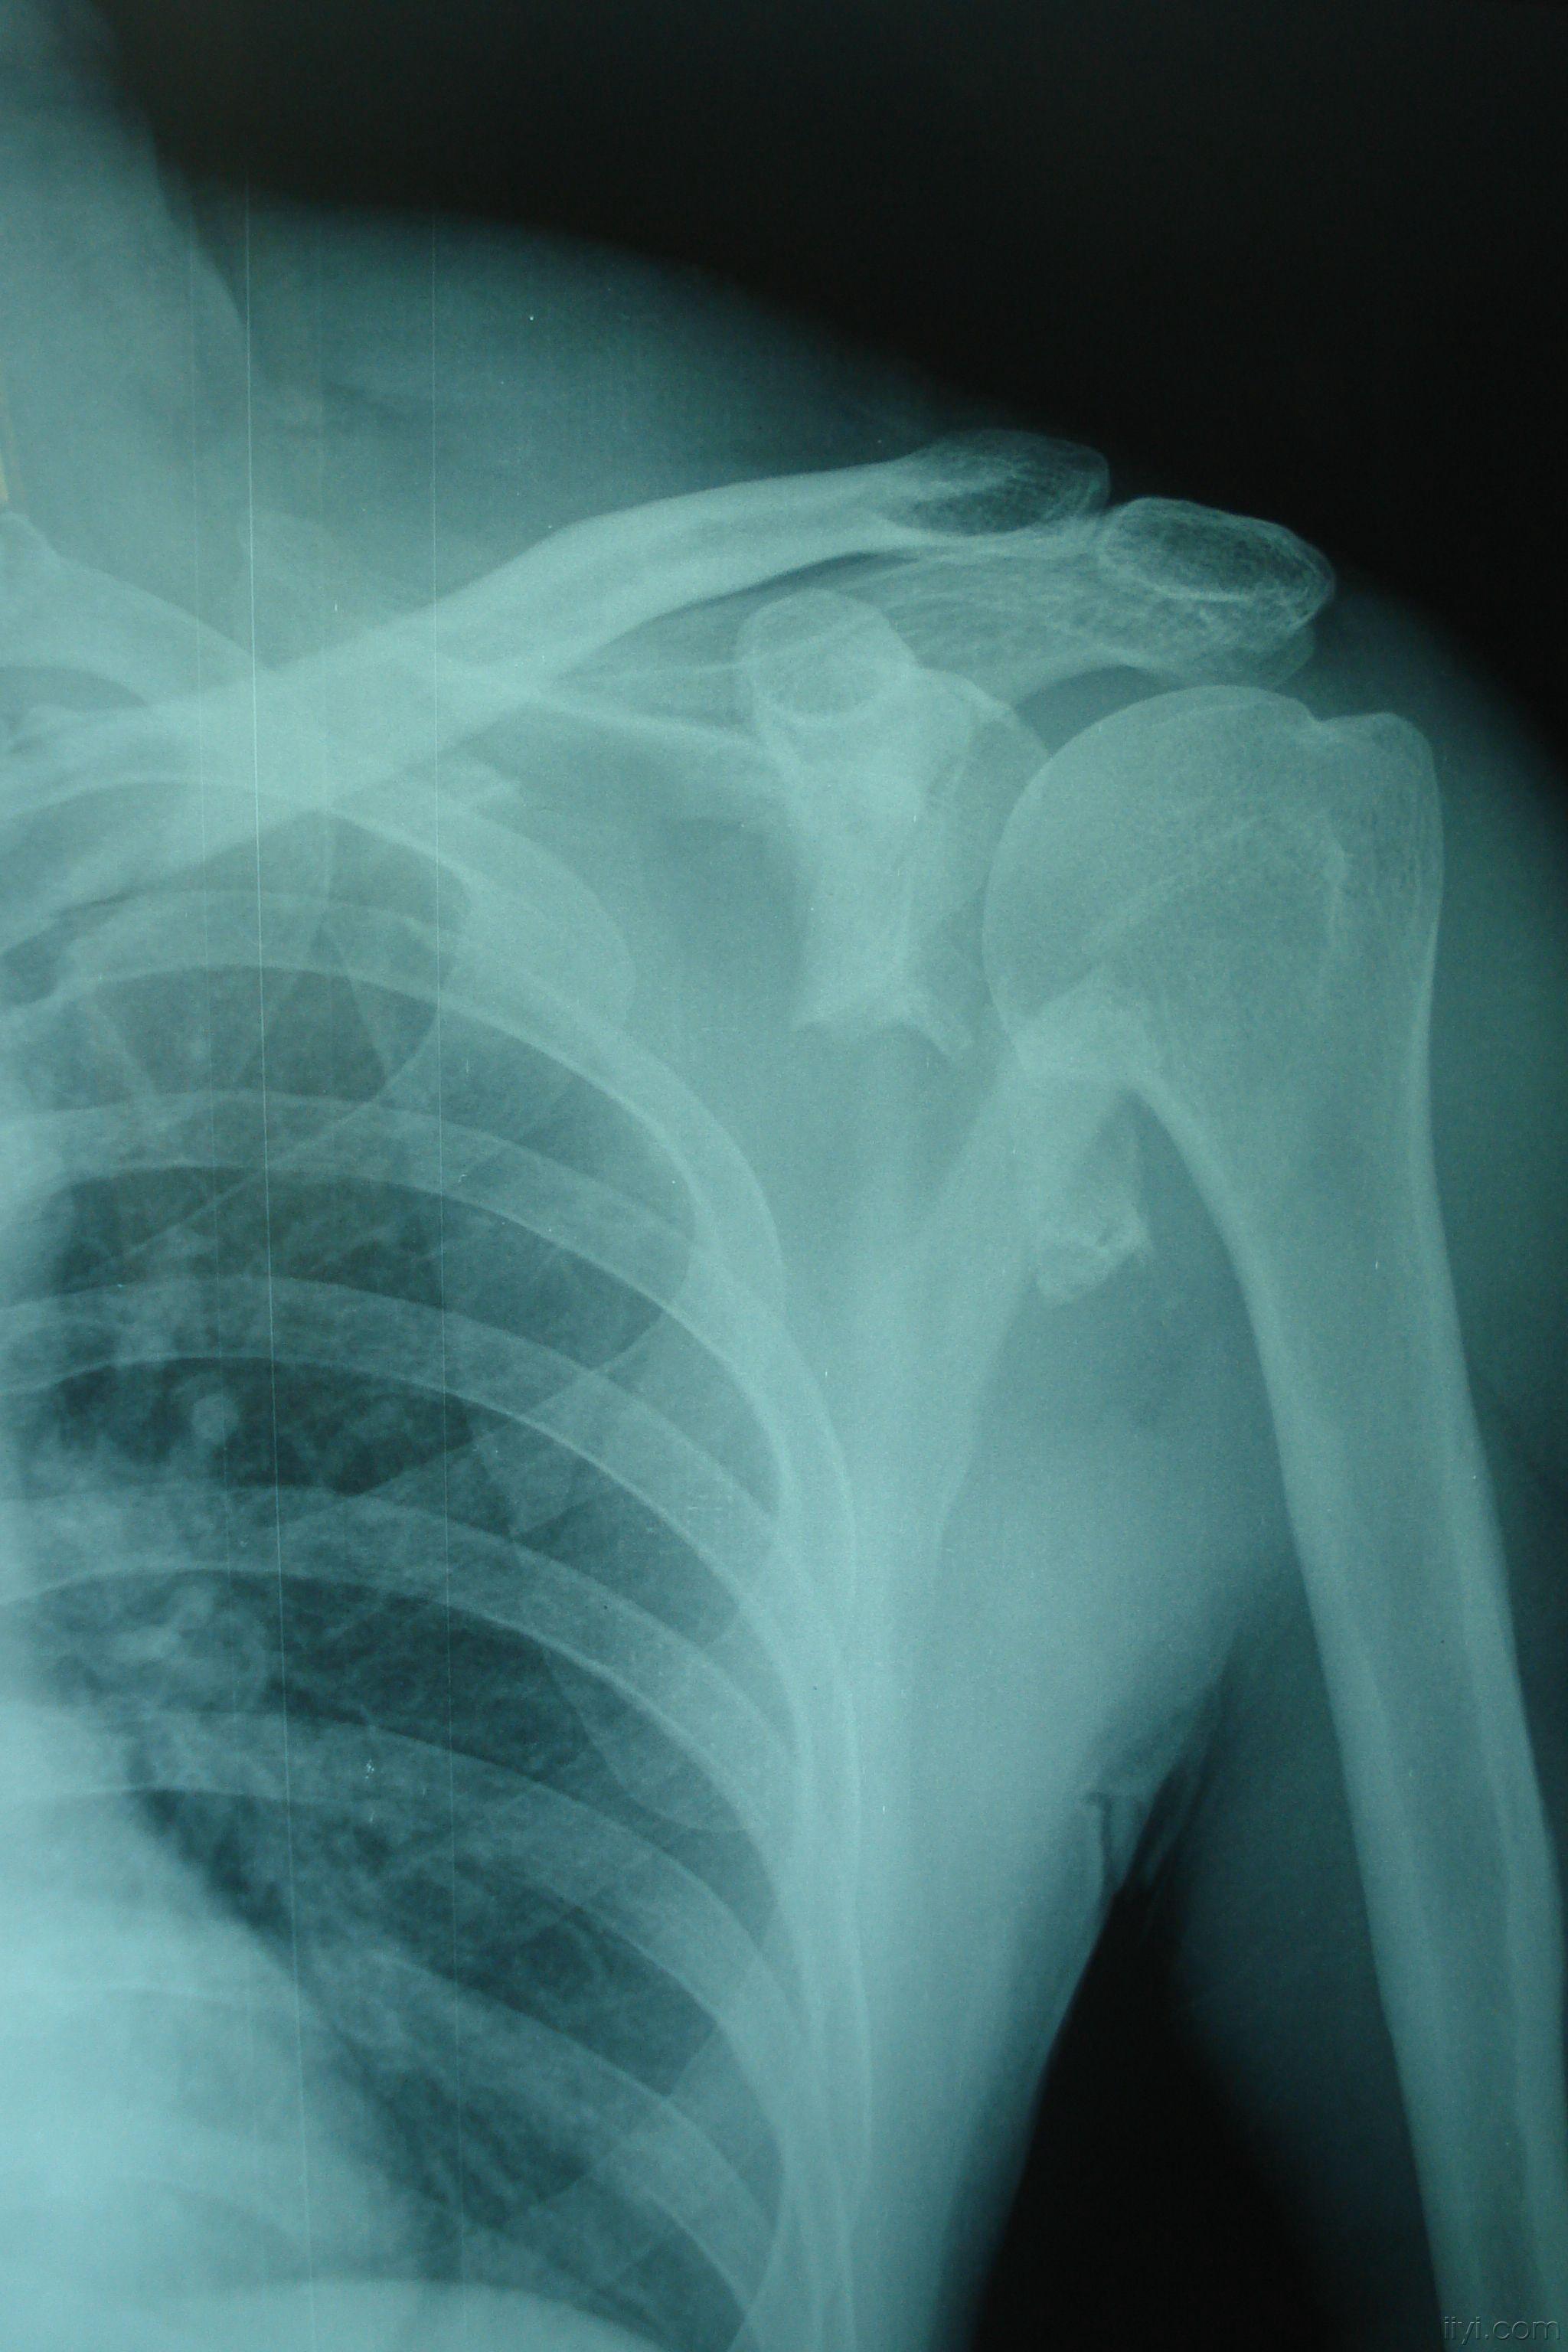

[localimg=400,267]6[/localimg][localimg=400,267]5[/localimg]患者男性,65岁,从2米高处摔下,左肩部着地,即感左肩部肿痛伴活动不利,当时无昏迷、无意识丧失,由家人送入院。

查体:左肩部肿胀,压痛明显,肩关节活动不利,指端血供、感觉、活动均正常。

初步诊断:左肩胛骨粉碎性骨折

讨论:1.可以保守治疗吗?肩胛骨骨折手术适应征?

2.手术切口如何选择?(肩胛体及关节盂同时显露内固定)

3.如何选择内固定?(肩胛体部最薄处只有2-3mm